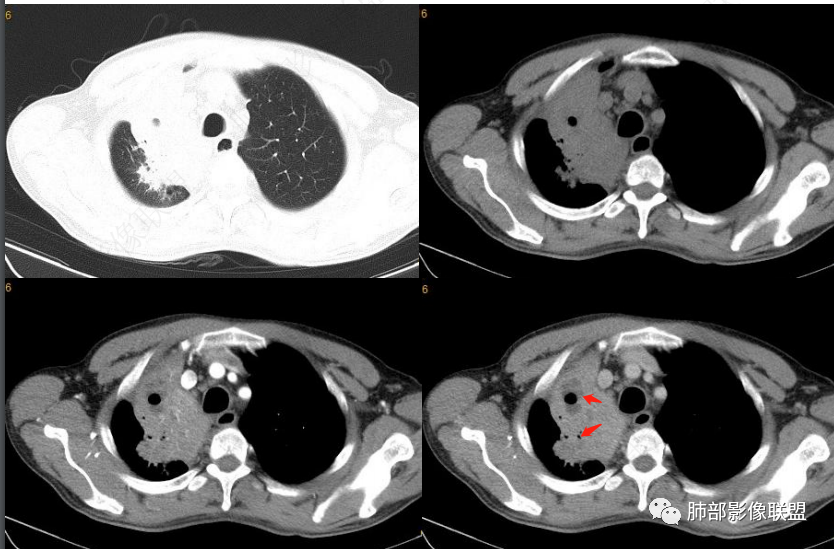

下图是炎性的

一般支气管狭窄一些,壁弥漫增厚

这是炎性特点,壁弥漫增厚,腔内粘液栓

这例也是,只是我调节不理想,壁其实也是弥漫增厚,腔狭窄,腔内粘液栓